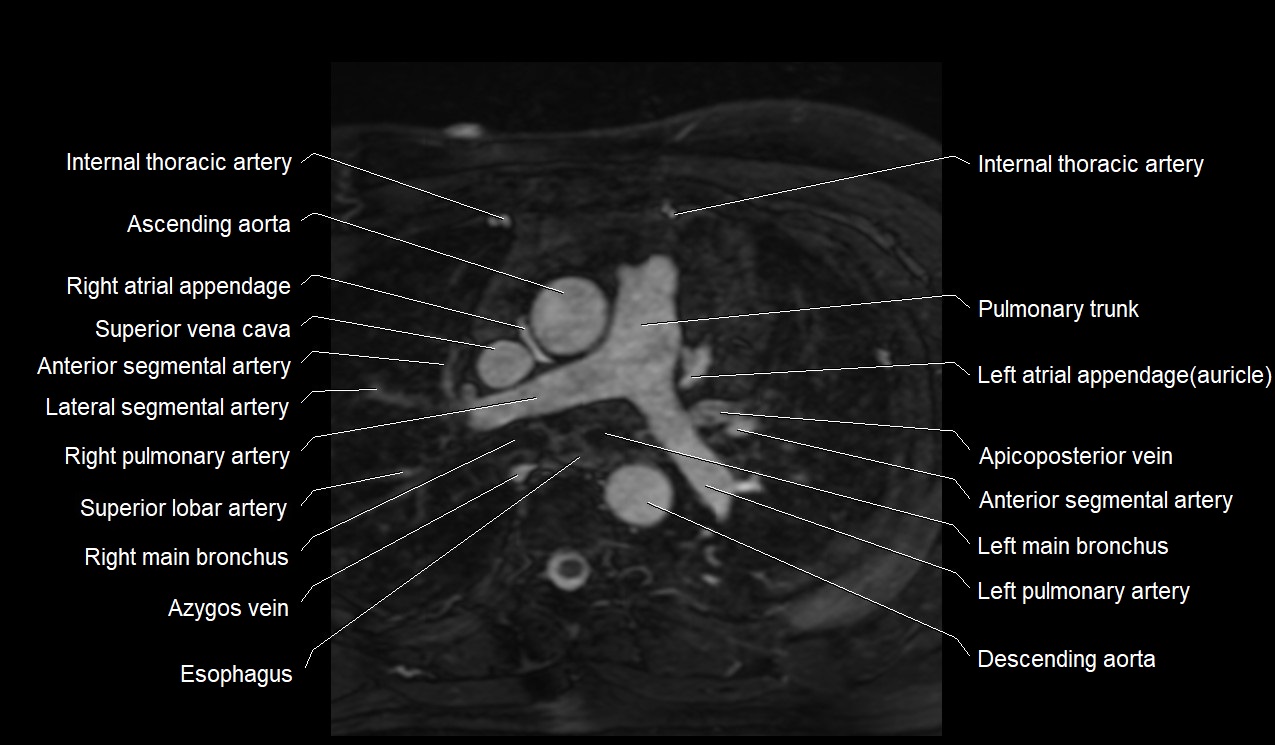

- Ascending aorta

- Pulmonary trunk

- Right pulmonary artery

- Left pulmonary artery

- Superior vena cava

- Azygos vein

- Left main bronchus